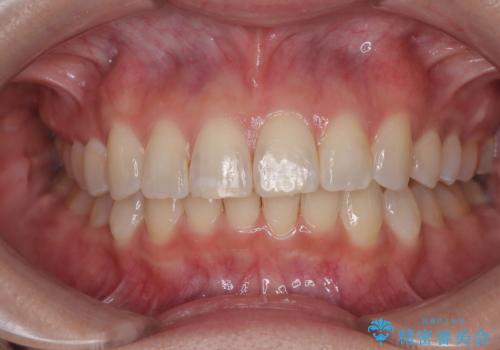

捻れて前に出ている前歯 ワイヤー装置での非抜歯矯正